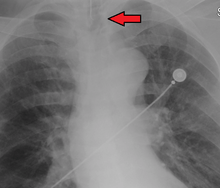

Ideally, at least one of the methods utilized for confirming tracheal tube placement will be a measuring instrument. Waveform capnography has emerged as the gold standard for the confirmation of tube placement within the trachea. Other methods relying on instruments include the use of a colorimetric end-tidal carbon dioxide detector, a self-inflating esophageal bulb, or an esophageal detection device.[33] The distal tip of a properly positioned tracheal tube will be located in the mid-trachea, roughly 2 cm (1 in) above the bifurcation of the carina; this can be confirmed by chest x-ray. If it is inserted too far into the trachea (beyond the carina), the tip of the tracheal tube is likely to be within the right main bronchus — a situation often referred to as a "right mainstem intubation". In this situation, the left lung may be unable to participate in ventilation, which can lead to decreased oxygen content due to ventilation/perfusion mismatch.[34]